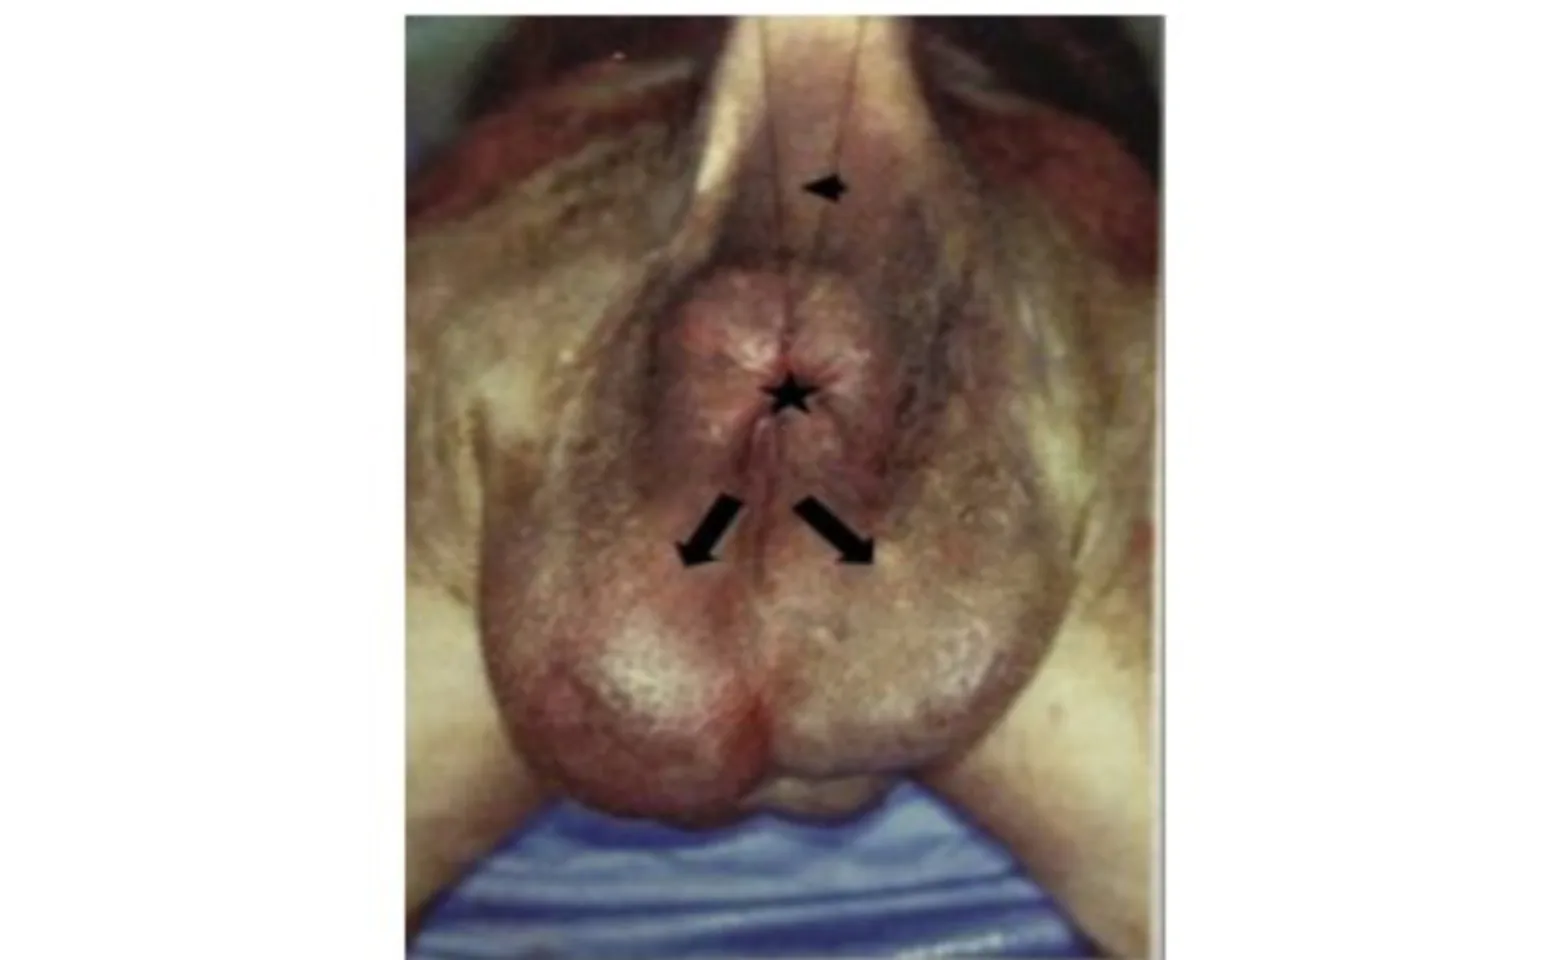

Figure 1: Hind end of a dog with tail raised (arrowhead) with bilateral perineal hernias (arrows) below the anus (star)

Most of the time, patients are presented for straining to defecate. Another common sign is a swelling seen next to or below the anus. Hernias are unilateral 50-66% of the time with the right side affected more often than the left. However, bilateral hernias can also occur. If there is a bilateral hernia, the entire perineal area will appear swollen (Figure 1). The swelling is typically soft and fluctuant and can be reduced with manual manipulation. A perineal hernia is diagnosed with a digital rectal exam. The herniated area feels thin sometimes the defect itself can be palpated. If organs like the urinary bladder or prostate have herniated, the swelling may feel hard and the patient may not be able to urinate. These cases, unlike most perineal hernias, are surgical emergencies (Figure 2).